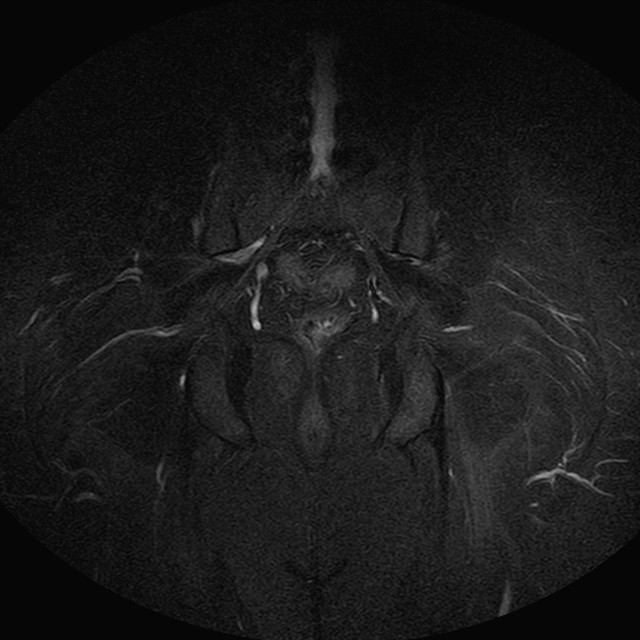

Esami: RMN BACINO

eSTIR

Evidenti e simmetriche alterazioni osteofitosiche in regione coxo femorale con riduzione delle rime articolari. Degenerazione completa del cercine glenoideo. Non attuali segni di versamento articolare. Non segni di edema osseo che escludono attuale algodistrofia od osteonecrosi. Lieve e simmetrica riduzione del trofismo della muscolatura glutea.